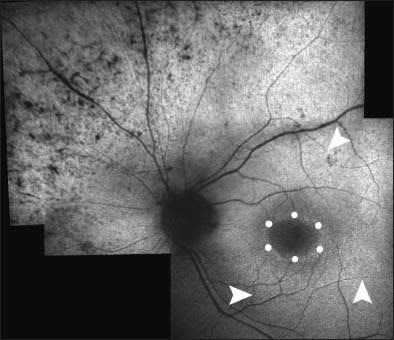

Autosomal recessive forms of retinal degeneration tend to be more severe, progress more rapidly, and present earlier than the AD forms (Figure 2). As stated previously, the AR inheritance pattern is characterized by sporadic appearance and occurrence in both men and women.

Figure 2. Autofluorescence image of a 36-year-old woman with autosomal recessive RP. Note the ring of hyperauto-fluorescence surrounding the macula (circles), attenuated arterioles (arrowheads), and pigmented hypoautofluorescent areas of atrophic RPE in the periphery.